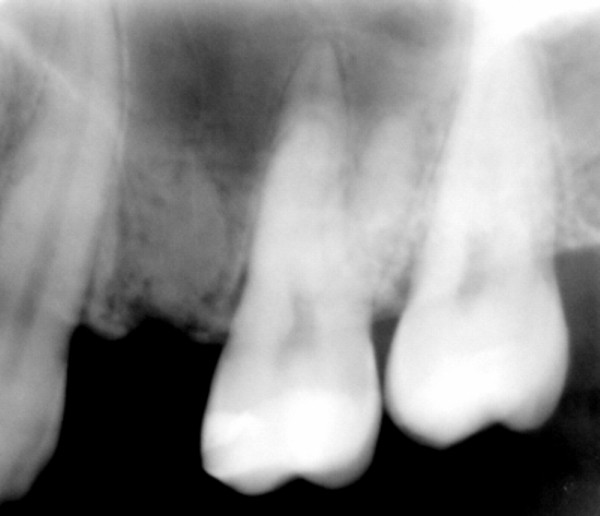

Porta radiografía panorámica (DIAPO 1), y teleradiografía , las que ofrecen una imagen francamente positiva para la instalación de Implante.

Todos estos parámetros fueron constatados por la toma de una imagen DIGORA (DIAPO 2), con una precisión tal , que corroboraba la visión de la claridad del caso

DIAPO 2

Sin más estudios, y convencidos del éxito del tratamiento, abordamos el mismo con las técnicas convencionales, y al realizar la periostotomía nos encontramos con un reborde acorde con los parámetros radiológicos.(DIAPO 3)

DIAPO 3

Nada más comenzar la insinuación del lecho implantario con la fresa lanceolada, ingresamos en una cavidad demasiado profunda que nos alarma y llama nuestra atención.

Agrandamos el diámetro de nuestra perforación, y observamos que carece su interior de fluidos sanguinolentos, purulentos o serosos, que puedan hacernos pensar en algún quiste residual, o entidad patológica alguna que pudiera haber pasado desapercibida a la observación clínica o radiográfica por omisión.(DIAPO 4)

Instalamos en su interior una galga de profundidad, ingresando esta en su totalidad.(DIAPO 5-6)

DIAPO 6

Estábamos en pleno Seno Maxilar.